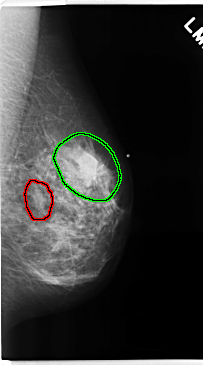

C_0229_1.LEFT_MLO

FILE: C_0229_1.LEFT_MLO.OVERLAY

TOTAL_ABNORMALITIES 2

ABNORMALITY 1

LESION_TYPE MASS SHAPE OVAL MARGINS CIRCUMSCRIBED

ASSESSMENT 3

SUBTLETY 5

PATHOLOGY BENIGN

TOTAL_OUTLINES 1

BOUNDARY

ABNORMALITY 2

LESION_TYPE MASS SHAPE IRREGULAR MARGINS SPICULATED

ASSESSMENT 5

PATHOLOGY MALIGNANT